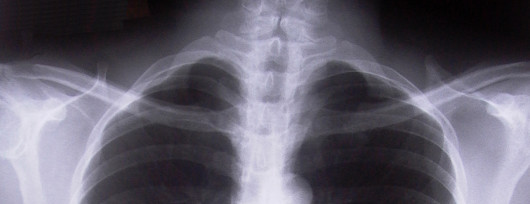

Udar, jak wyjaśniała prof. Członkowska w 80 proc. przypadków wynika z niedokrwienia części mózgu, w 15 proc. – z krwotoku na skutek pęknięcia tętnicy w mózgu, a w 5 proc. przypadków chodzi o krwotok podpajęczynówkowy.